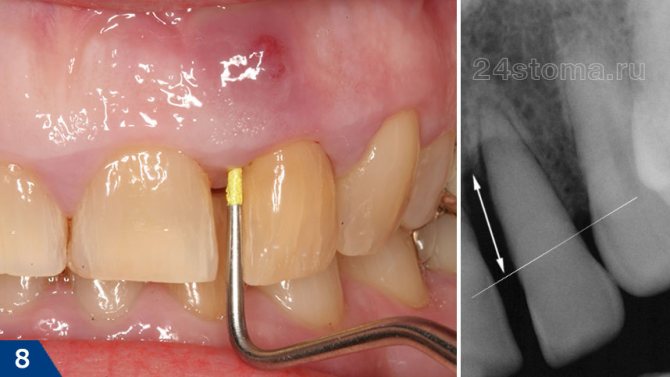

Свищ на десне – это всегда симптом гнойного воспаления, протекающего в области корня одного из зубов (рис.1-2). Чаще всего свищи образуются на фоне обострения апикального периодонтита. Это заболевание зуба чаще всего является следствием невылеченного вовремя кариеса и пульпита, и при нем у верхушки корня зуба формируется очаг хронического воспаления. Обычно такое хроническое воспаление протекает бессимптомно, но при переохлаждении или снижении иммунитета может происходить обострение – с формированием гноя в очаге воспаления.

Образование гноя в ряде случаев приводит к формированию в кости свищевого хода, который открывается на поверхности десны свищевым отверстием. Соответственно, из свищевого отверстия в полость рта будет выделяться образующийся в очаге воспаления гнойный экссудат. Как правило, свищевое отверстие располагается на десне всегда в проекции корня причинного зуба. У большинства пациентов появлению свища всегда предшествует болезненность при накусывании в одном из зубов. После формирования свищевого отверстия обычно боль сразу исчезает.

Свищ на зубе выявляется при визуальном осмотре. Чтобы оценить состояние процесса, понять до какой глубины дошло поражение, определить интенсивность заболевания – врач назначает проведение рентгенологического исследования.